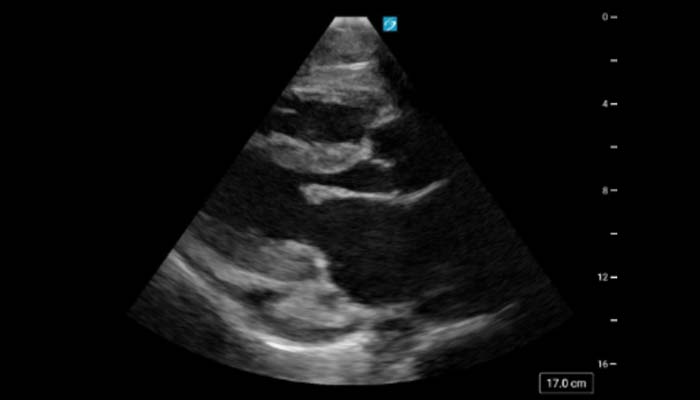

Point of care ultrasonography (POCUS) refers to the practice of using ultrasound at bedside to assist in medical diagnosis and procedures. While initially having presence in the fields of critical care and emergency medicine, POCUS is rapidly becoming a growing skill in general internal medicine and hospital medicine as well. There is now great interest in incorporating POCUS training into medical education at both the medical student and resident levels.

The point of care ultrasound longitudinal three-year pathway allows for select residents with great interest in POCUS to hone their abilities through formal training and assessments, journal clubs, and simulation sessions. Additionally, the pathway provides networking opportunities as well as opportunities to teach various POCUS related topics. While all IM residents will be exposed to ultrasound, pathway members will take a deeper dive into the field as they develop robust image portfolios, connect imaging findings with diagnostic skills, and involve themselves in scholarly projects.